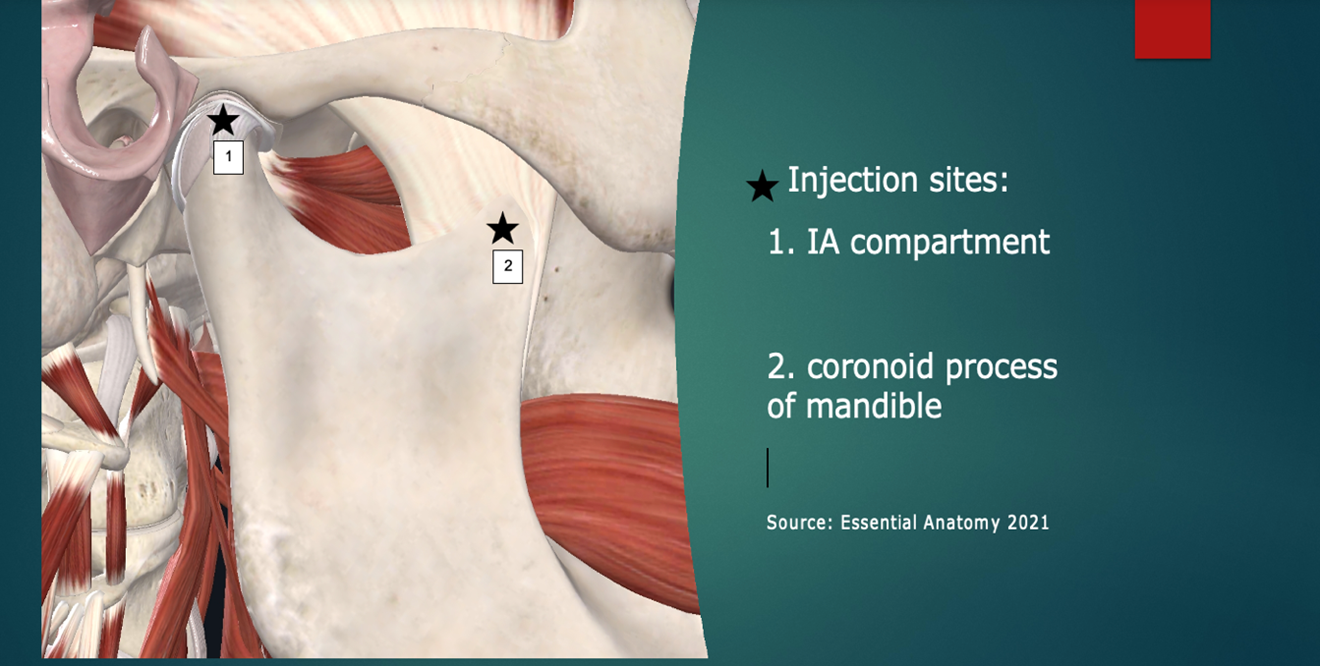

The two highest yield injection sites in my experience are illustrated in Figure 2: The intra-articular compartment and the coronoid process attachment of the temporalis tendon (enthesis).9

Following this, the probe is rotated 90 degrees to a transverse orientation. The mandibular coronoid process enthesis is then injected out of plane with 0.5 ml injectant. (Figures 6 and 7).

Figure 2: Injection sites (simplified “Louw Method”). Image courtesy of Complete Anatomy, https://3d4medical.com/